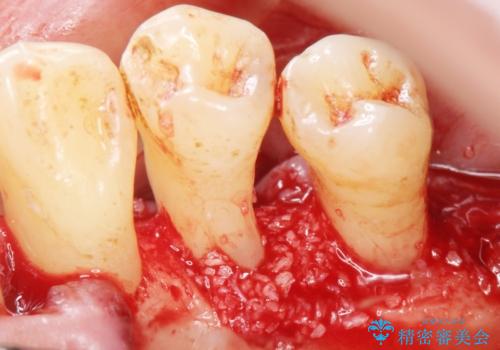

精査したところ、全顎的な重度の歯周病により右下の小臼歯(右下4)激しい動揺を認めました。

できるだけ自分の歯を残したいという患者様の強いご希望により、禁煙指導後再生療法(骨を増やす手術))を行いました。

再生療法から1年後リエントリー手術により骨の再生を確認し、骨外科処置(骨を平らにして歯周ポケットの根本的な改善を図る処置)を行ったのち、連結補綴を行いました。